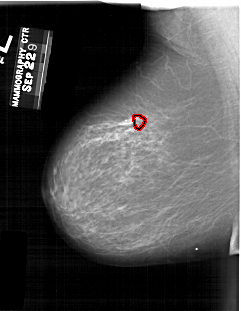

A_1260_1.LEFT_MLO

LEFT_MLO LINES 5896 PIXELS_PER_LINE 4561 BITS_PER_PIXEL 12 RESOLUTION 43.5 OVERLAY

FILE: A_1260_1.LEFT_MLO.OVERLAY

TOTAL_ABNORMALITIES 1

ABNORMALITY 1

LESION_TYPE MASS SHAPE ARCHITECTURAL_DISTORTION MARGINS ILL_DEFINED

ASSESSMENT 4

SUBTLETY 2

PATHOLOGY MALIGNANT

TOTAL_OUTLINES 1

BOUNDARY